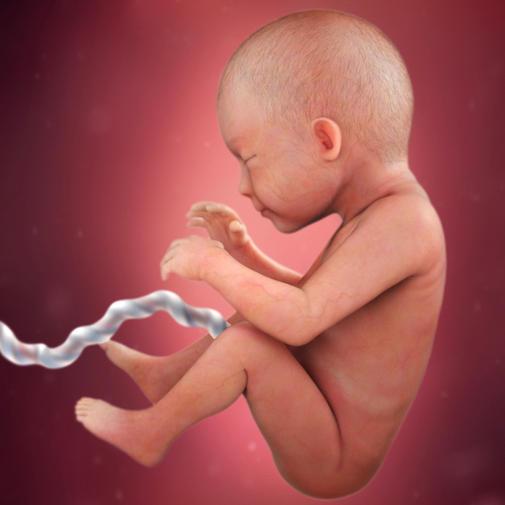

Ve 29. týdnu těhotenství měří plod zhruba 39 cm. Pro určení délky plodu se nyní používá součet délky hlavičky, trupu a nohou. Váha plodu je nyní zhruba 1150 g.